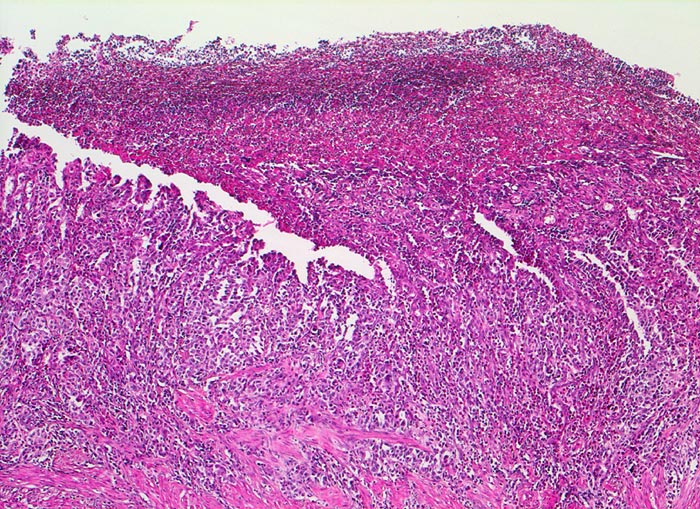

Bei Magenfrühkarzinomen findet sich häufiger ein intestinaler als ein diffuser Typ nach Lauren (Magenkarzinom vom diffusen Typ siehe Differentialdiagnose). Beim intestinalen Typ ist das Tumorgewebe relativ scharf gegenüber der Umgebung abgegrenzt und zeigt meist tubuläre Tumorformationen, die von Zylinderepithel ausgekleidet werden. In der Nachbarschaft von Magenkarzinomen des intestinalen Typs finden sich gehäuft Dysplasien als sogenannte Ausläuferläsionen oder schwere Formen der chronisch atrophen Gastritis mit intestinaler Metaplasie ( 1302).

Am unteren Ende des Präparates Antrummukosa mit mässiggradiger chronischer, geringgradig aktiver Gastritis und ausgedehnter intestinaler Metaplasie (Becherzellen).

Weiter oben Invasion der Magenschleimhaut durch ein teils solides, teils drüsenbildendes Adenokarzinom mit stark atypischen Tumorzellen.

Fokale Erosion des Karzinoms bedeckt von fibrinoleukozytärer Membran.

Tumorinfiltration der Submukosa an der oberen Präparathälfte.

Tumorfreie Lamina muscularis propria.